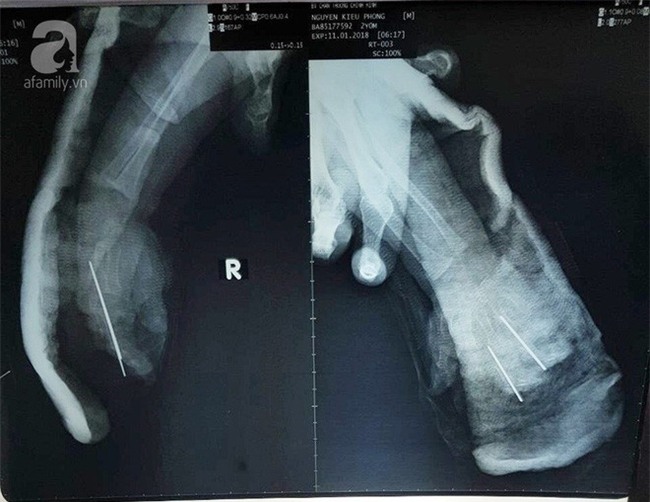

BS Võ Hoà Khánh, bệnh viện Chấn thương Chỉnh hình TP.HCM cho biết, bệnh nhi P nhập viện trong tình trạng bàn tay phải đứt lìa, dập nát các ngón và đứt 4/5 ngón, tay nhiều dầu nhớt, đứt nhiều tầng. Người nhà cho biết bé bị dây xích xe máy quấn đứt lìa.

Ngay lập tức, ekip điều trị đã tiến hành gây mê nội khí quản, cắt lọc, nối ghép vi phẫu, nối gân ở bàn tay bị đứt. Sau hơn 6 giờ phẫu thuật, các bác sĩ đã giữ được bàn tay và hai ngón tay cho bệnh nhi. Đến ngày 15-1, các ngón tay đã hồng ấm nhưng bàn tay vẫn còn nẹp bột và phải tiếp tục theo dõi.